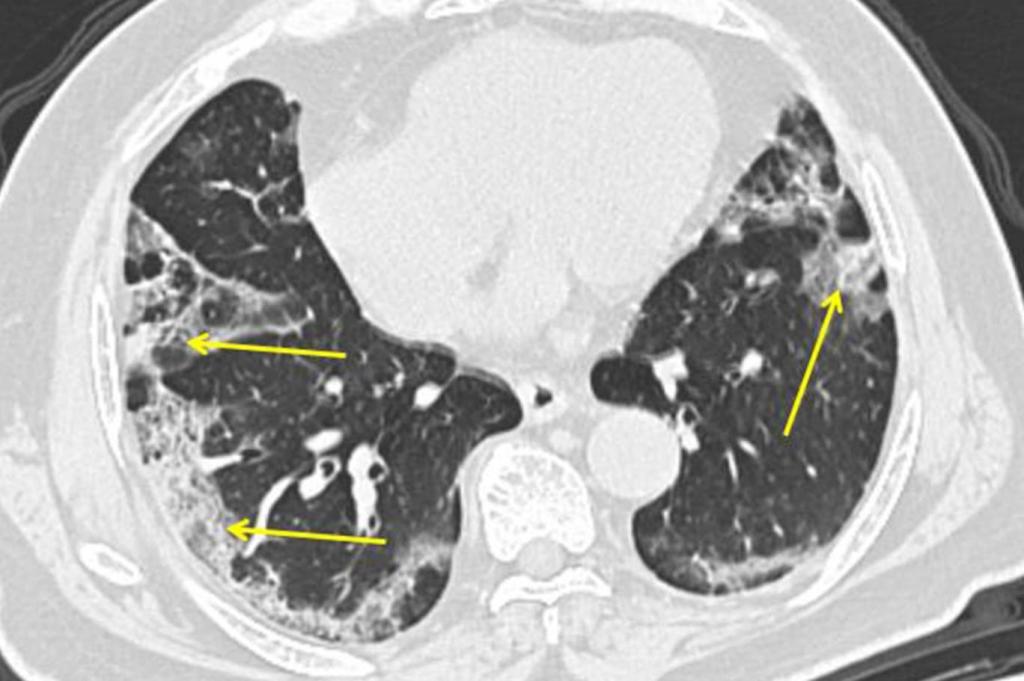

koronavirüs